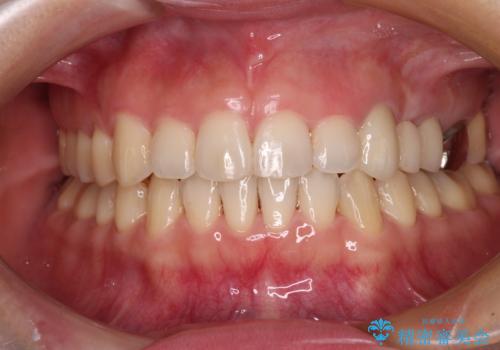

矯正治療後には切断したブリッジをオールセラミックブリッジに置き換えることとしました。

矯正治療中に上下前歯が接触しない時期があり、咬み合わせ改善のために期間がかかるのではないかと懸念されましたが、結果的には補綴治療も含めて1年以内の短期間で終えることができました。